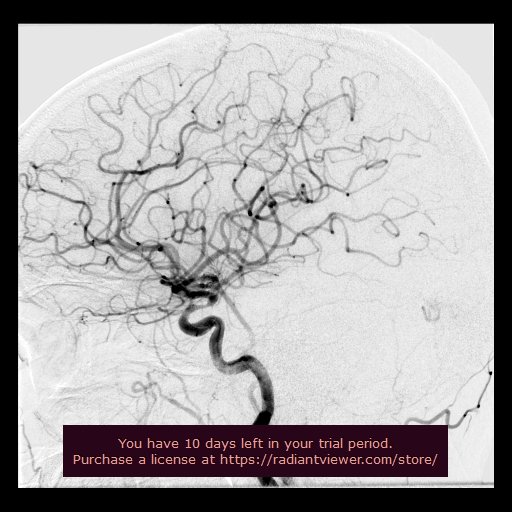

BRAIN ANGIOGRAPHY